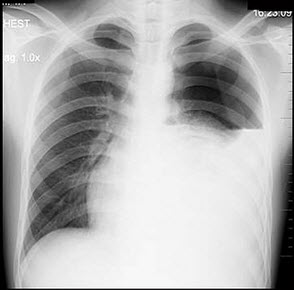

12、单项选择题

男性患者,32岁,两天前被人踢伤胸部,逐渐感胸闷,呼吸困难,X线检查如图,最佳诊断为()

A.左侧气胸

B.左侧胸腔积液

C.左侧胸膜肥厚

D.左侧液气胸

E.左侧肺不张

13、单项选择题

患者男性,18岁,感胸闷气逼,胸片检查见图,最合理的诊断是()

A.左侧胸膜肥厚

C.左侧液气胸

D.左侧肺不张

E.左侧气胸